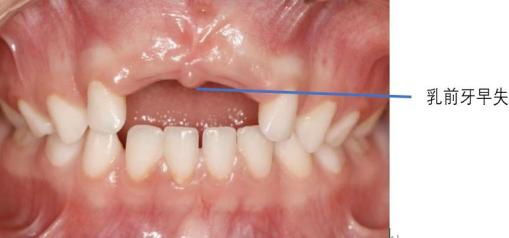

4.乳牙早失诱发错颌畸形

如果牙齿因严重破坏而无法保留被拔除,或者自行脱落过早,旁边的牙齿就会向这个空隙倾斜,导致后继恒牙的萌出空间不足,需要通过矫正来解决这个问题。

3.影响发音和美观

前牙的缺失或损坏会影响孩子发音的清晰度,也可能因牙齿不好看而被同伴取笑,影响自信心和社交。